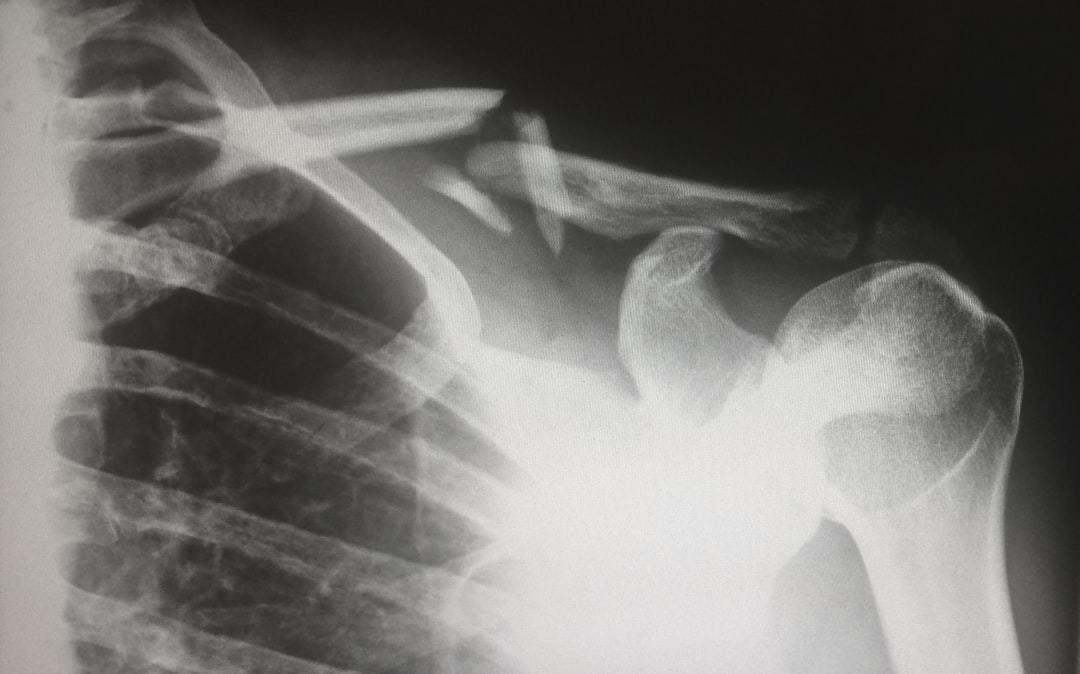

1988ๅนดๆ็ฅ็็ใพใใ2007ๅนดๅคฉ็ๅคงๅญฆๅจๅญฆไธญใซใขใกใชใซใณใใใใใผใซใฎ่ฉฆๅไธญใฎไบๆ

ใง้ ๆคใ้ชจๆใ่ปๆค